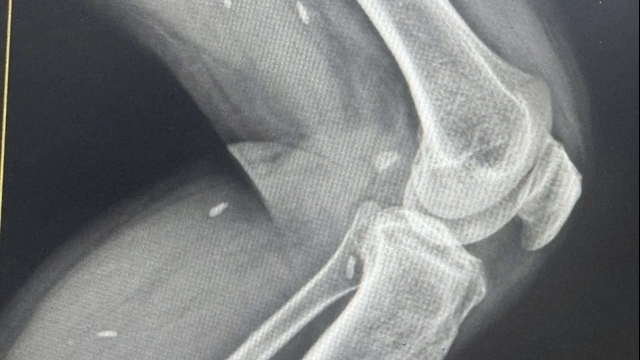

Tại đây, cùng với cho trẻ uống 2 loại kháng sinh phối hợp chống viêm, các bác sĩ chỉ định cho bệnh nhi chụp X-quang sọ não. Qua hình ảnh chụp mặt thẳng và nghiêng, các bác sĩ phát hiện có hình ảnh cản quang tại vị trí hốc mũi phải, xác định có dị vật trong mũi; đồng thời chỉ định nội soi gắp ra dị vật.